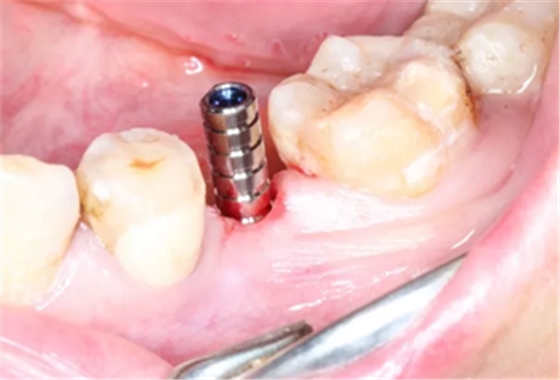

4.在全程导板的引导下,使用全程导板工具盒中的携带器,从导板套环孔处将植体植入,直至携带器的六角、与导板套环的六角严丝合缝(如图,六角对六角),即表示植体就位成功。

术前术后CBCT数据对比分析,植体就位准确。